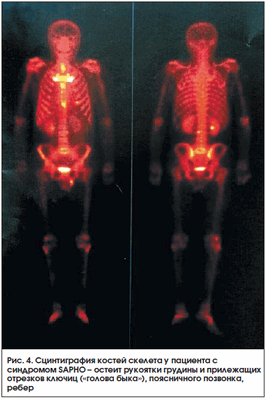

Синдром SAPHO (Synovitis, Acne, Pustulosis, Hyperostosis, Osteitis) характеризуется кожными проявлениями (ладонно-подошвенный пустулез и/или тяжелое акне) и изменениями в костях (остеит) и суставах (артриты). Данный синдром в связи с множественностью жалоб, разнообразием клинических и рентгенологических проявлений в костной системе может диагностироваться с большим запозданием. Сцинтиграфия костей скелета во многих случаях является методом, дающим достаточную информацию для постановки диагноза. Наибольшее накопление РФП при сцинтиграфии отмечается в зонах усиленного метаболизма кости (остеит) - обычно в костях, образующих грудино-ключичные («голова быка») и грудино-реберные сочленения [33]. Весьма специфичен высокий уровень накопления в трубчатых костях, что чаще встречается у детей (рис. 3, 4).